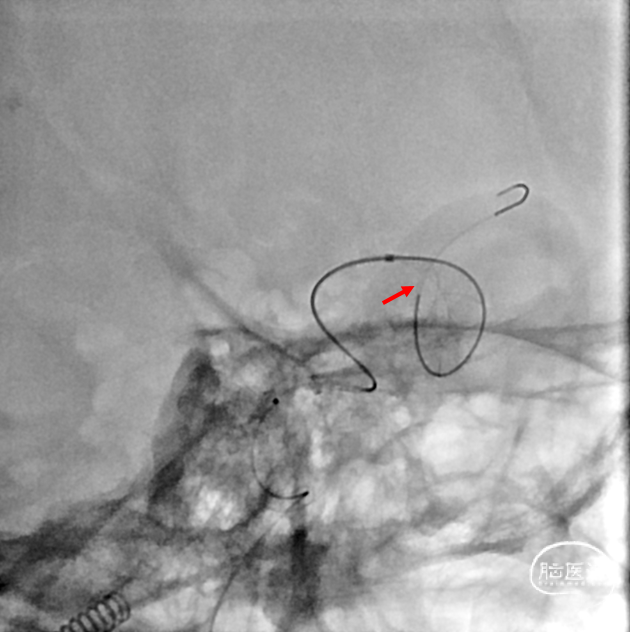

支架打开不良

支架重新打开良好

再次交换3m Floppy

Maverick 2mm/15mm,6atm